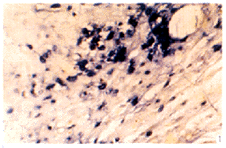

图1 单纯载体组术后10 d TNF-α mRNA阳性表达

Fig 1 Positive expression of TNF-α mRNA in BMP 0 mg group at 10th day ISH ×400

, http://www.100md.com

图2 单纯载体组术后10 d IL-6 mRNA阳性表达

Fig 2 Positive expression of IL-6 mRNA in BMP 0 mg group at 10th day ISH ×400

图3 复合BMP 2 mg组术后10 d TNF-α mRNA阳性表达

Fig 3 Positive expression of TNF-α mRNA in BMP 2 mg group at 10th day ISH ×400

图4 复合BMP 2 mg组术后10 d IL-6 mRNA阳性表达

Fig 4 Positive expression of IL-6 mRNA in BMP 2 mg group at 10th day ISH ×400

原位杂交检测图像分析结果见Tab 1. 结果发现, 植骨术后, 各组植骨局部均可见TNF-α和IL-6 mRNA的阳性表达, 但表达强度不同. 不同时间点各组间TNF-α和IL-6 mRNA表达强度有显著性差异(P<0.01), 其中以B0组表达最强(Fig 1, 2), B2组表达最弱(Fig 3, 4), 此表明载体中BMP对TNF-α和IL-6 mRNA表达有抑制作用, 并呈剂量依赖关系.